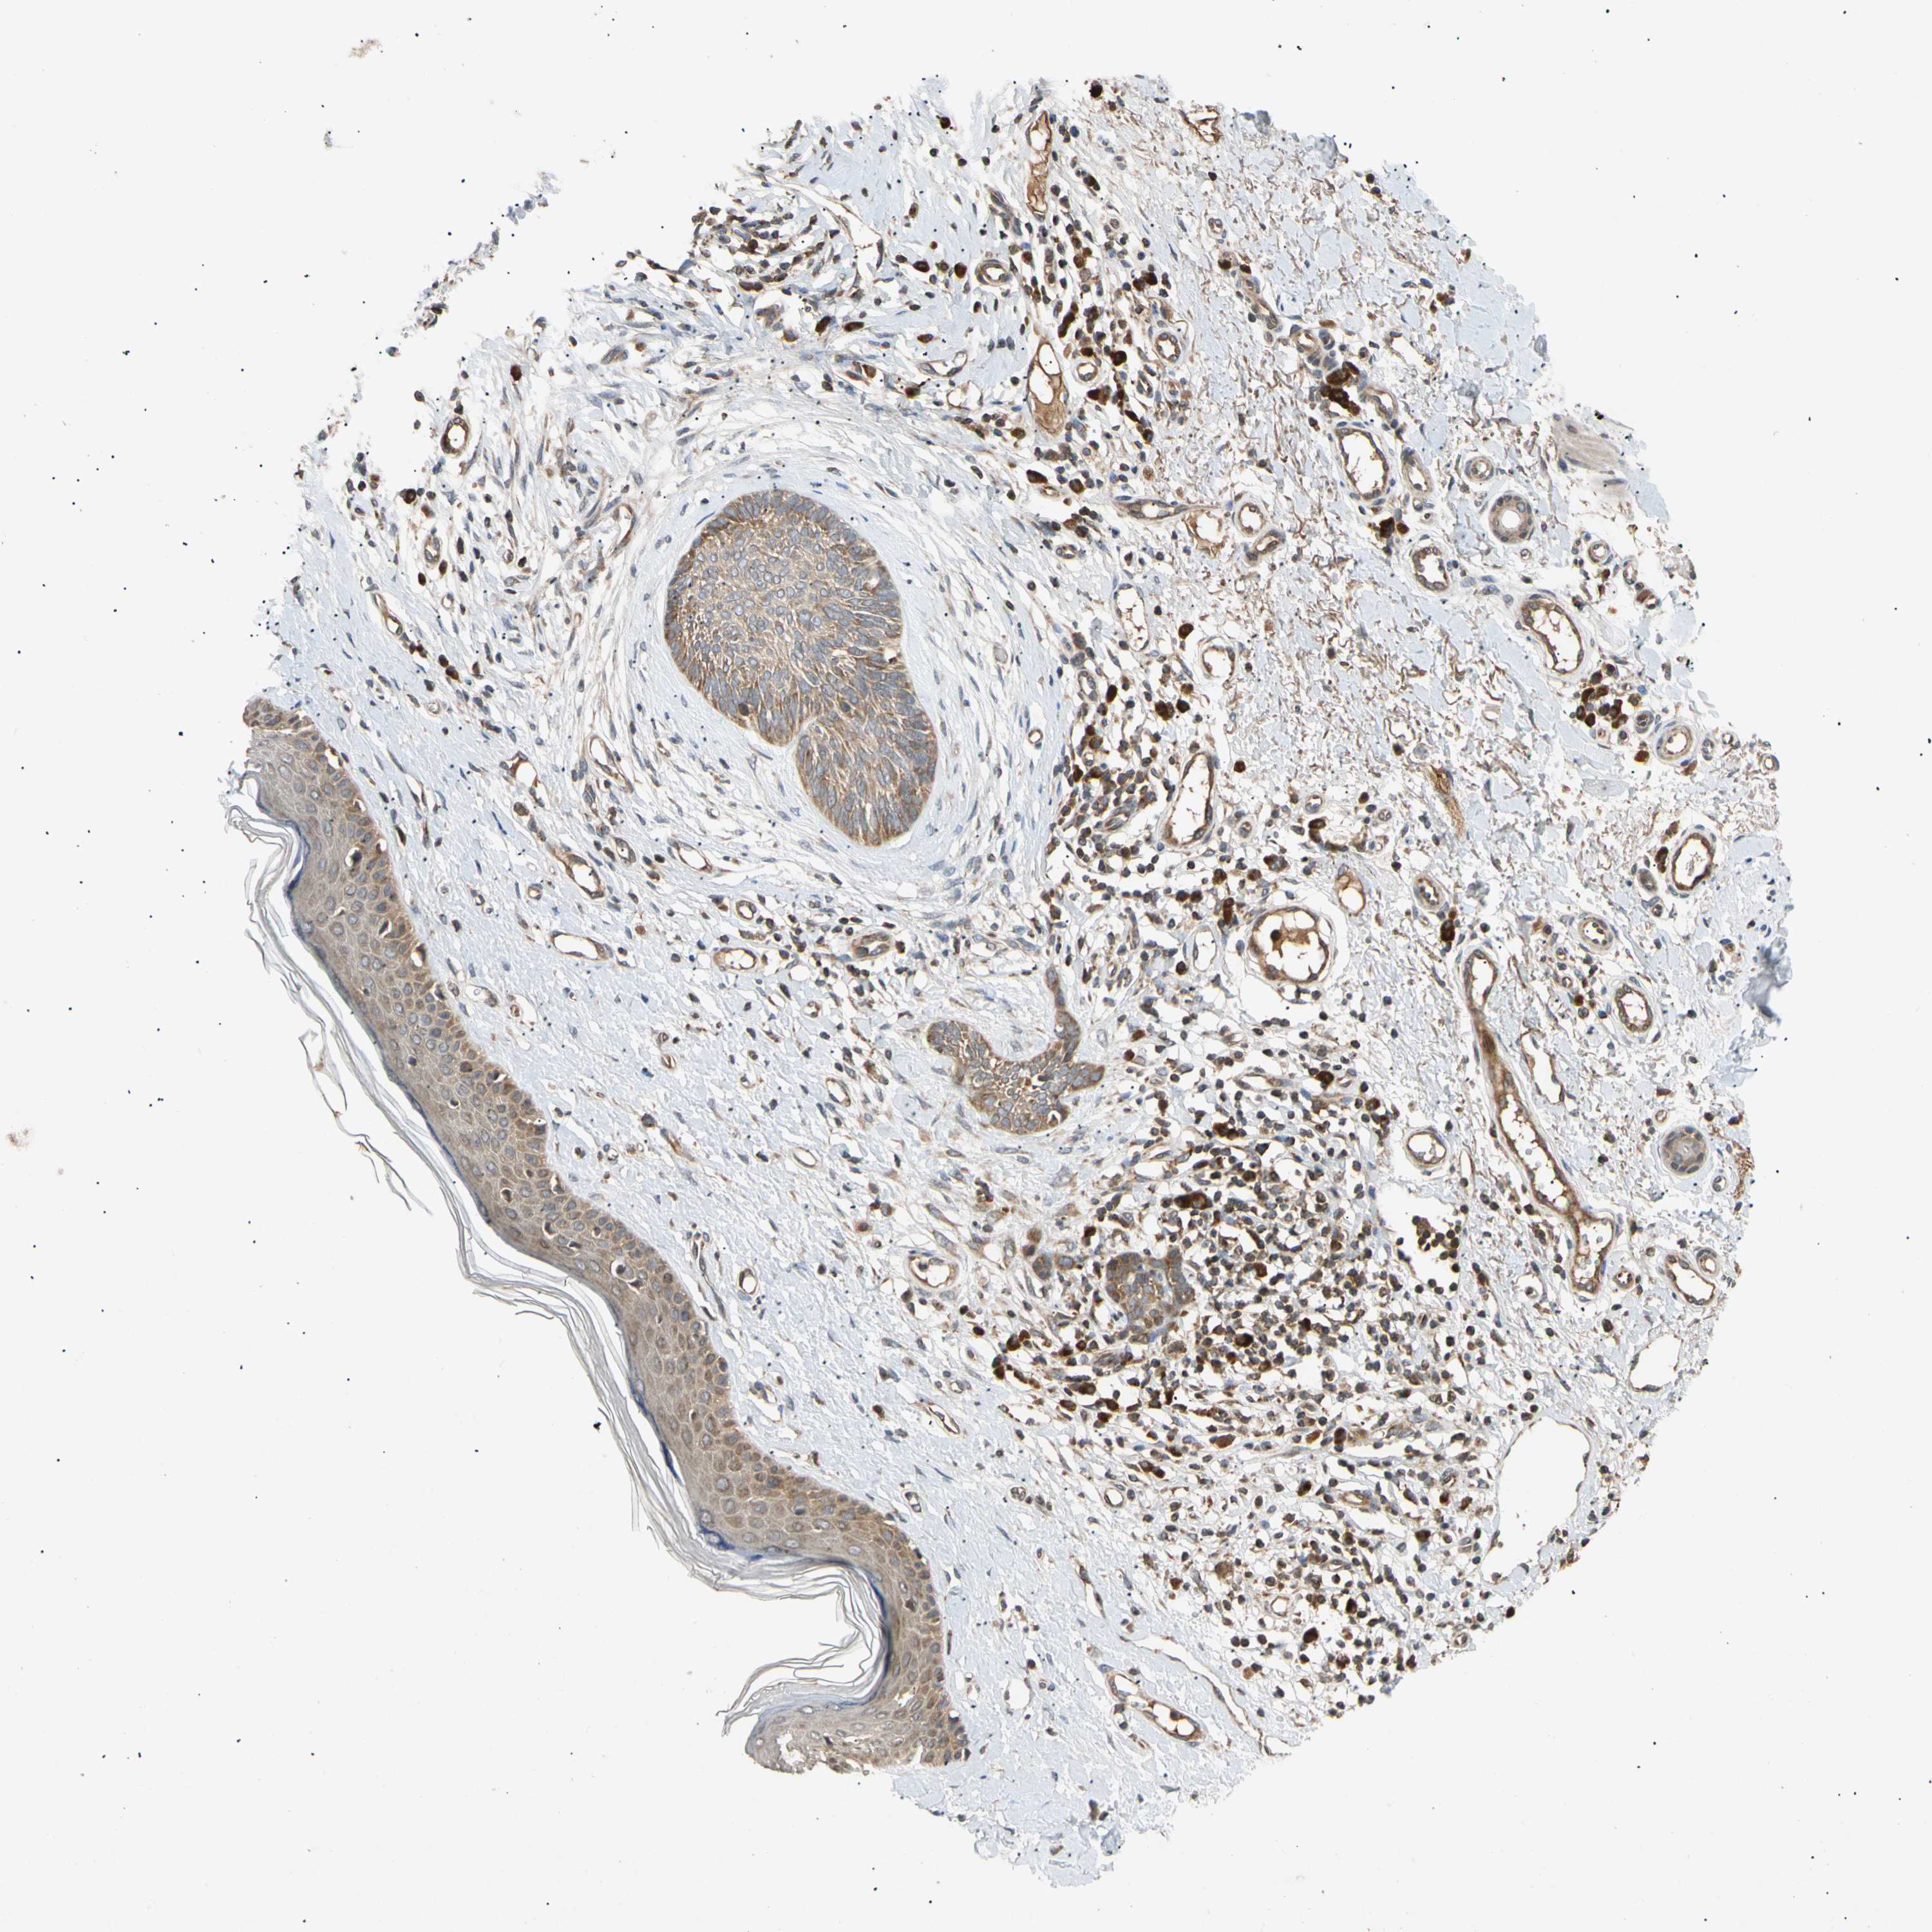

Basal cell and squamous cell cancer

SKIN CANCER - Protein expressioni

A mouse-over function shows sample information and annotation data. Click on an image to view it in a full screen mode. Samples can be filtered based on level of antibody staining by selecting one or several of the following categories: high, medium, low and not detected. The assay and annotation is described here.

Antibody stainingi

Antibody staining in the annotated cell types in the current human tissue is reported as not detected, low, medium, or high, based on conventional immunohistochemistry profiling in selected tissues. This score is based on the combination of the staining intensity and fraction of stained cells.

Each image is clickable and will lead to virtual microscopy that enables deeper exploration of all samples and also displays staining intensity scores, fraction scores and subcellular localization as well as patient and tissue information for each sample.

Antibody HPA006083

Squamous cell carcinoma, NOS

Basal cell carcinoma